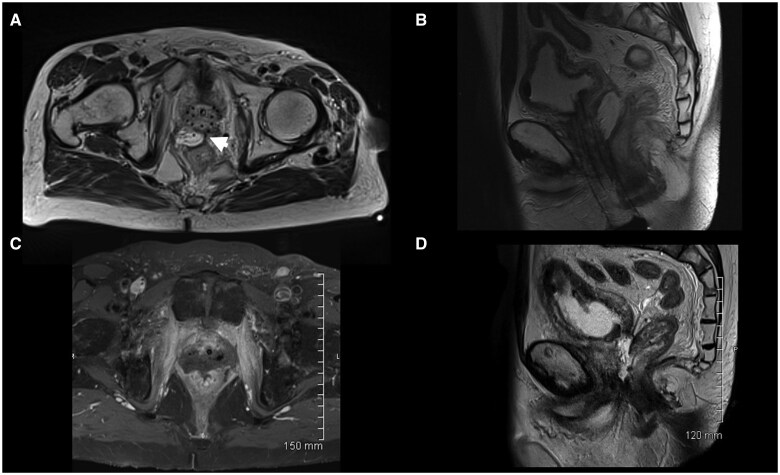

有盆腔放射史的前列腺癌患者的放射治疗可能受到直肠剂量限制和直肠毒性风险的限制。直肠间隔剂已被证明可以改善前列腺癌治疗中的直肠剂量学。本研究旨在评估先前接受过放射治疗的前列腺癌患者在直肠和前列腺之间放置水凝胶间隔物(特别是SpaceOAR)的安全性和结果。在这个回顾性的病例系列中,我们分析了8例连续接受盆腔放疗或盆腔放疗的患者的医疗记录,这些患者接受过经会阴SpaceOAR安置。我们记录了SpaceOAR放置后、放疗前后的并发症发生率。在这个患者队列中有一系列的并发症,从盆腔疼痛到更严重的并发症,如直肠穿孔、脓肿和瘘管。8例患者中2例出现严重并发症。再照射可能增加正常组织并发症的风险;然而,在一小部分患者中,使用SpaceOAR放置水凝胶垫片治疗既往盆腔放疗的前列腺癌患者,其直肠并发症的发生率高于预期。我们强烈建议在此患者组中谨慎使用SpaceOAR。

Treating prostate cancer with radiation therapy in patients with a history of prior pelvic radiation may be limited by rectal dose constraints and the risk of rectal toxicity. Rectal spacers have been shown to improve rectal dosimetry in the treatment of prostate cancer. This study aimed to evaluate the safety and outcomes of hydrogel spacer placement, specifically SpaceOAR, between the rectum and prostate in prostate cancer patients who had previously undergone radiation therapy. In this retrospective case series, we analysed the medical records of 8 sequential patients undergoing reirradiation in the setting or prior pelvic radiation, who had received transperineal SpaceOAR placement. We documented the incidence of complications after SpaceOAR placement, before and after undergoing radiation therapy. There was a spectrum of complications in this patient cohort, ranging from pelvic pain to more severe complications such as rectal perforation abscess and fistula. Severe complications occurred in 2 of the 8 patients. Re-irradiation may increase the risk of normal tissue complications; however, hydrogel spacer placement using SpaceOAR in prostate cancer patients with prior pelvic radiation was associated with a higher rate of rectal complications than expected in a small series of patients. We urge caution when using SpaceOAR in this patient group.